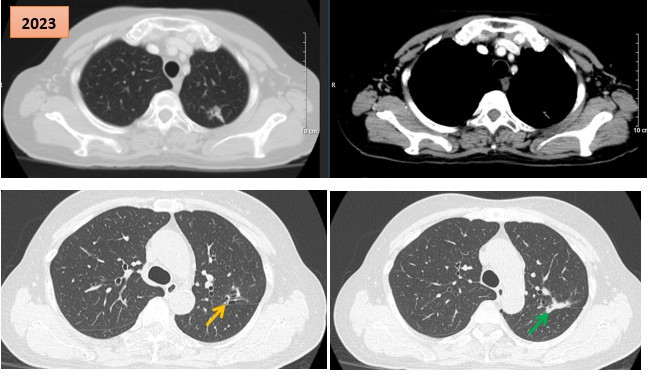

Thuốc điều trị đích giúp bệnh nhân ung thư phổi giai đoạn muộn ổn định bệnh suốt 6 năm

Thứ Sáu, ngày 30/01/2026 10:04Các bác sĩ Trung tâm Y học hạt nhân và Ung bướu (Bệnh viện Bạch Mai) vừa ghi nhận một trường hợp bệnh nhân ung thư phổi giai đoạn muộn được điều trị bằng thuốc TKIs thế hệ I từ năm 2017...